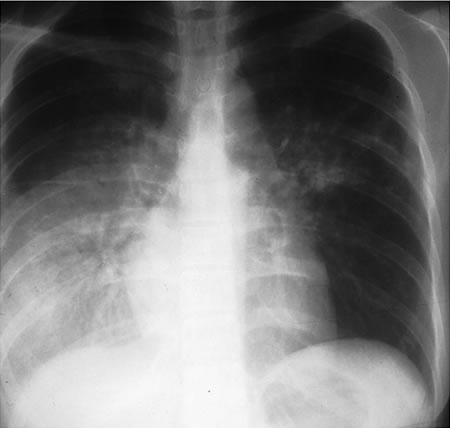

[Figure caption and citation for the preceding image starts]: Right hilar adenopathy in a childFrom the personal collection of David Horne and Masahiro Narita; used with permission [Citation ends].